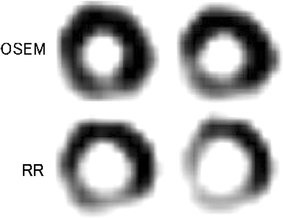

We retrospectively reviewed myocardial SPECT images of 60 consecutive patients (26 men, 34 women; mean age 68 years). They consisted of 25 with coronary artery disease (CAD) and 35 without, as confirmed by the coronary angiography (CAG). The patients had undergone myocardial perfusion SPECT imaging with thallium-201 (111 MBq) under an exercise or pharmacological stress protocol. Two readers reviewed the myocardial SPECT images for the presence of CAD on a 4-point scale where 0 = normal, 1 = probably normal, 2 = probably abnormal, and 3 = abnormal. Three reading sessions were held: first, ordered subsets expectation maximization (OSEM) SPECT images, second, OSEM with RR images, and third, both OSEM and RR images. Diagnostic performance for accuracy of coronary arterial stenoses was compared for OSEM, RR and both the images.

The sensitivity increased using RR images, but specificity decreased, and thus overall diagnostic accuracy was decreased, as compared with using OSEM images. The overall accuracy of using both the images showed the highest diagnostic performance among the three sets of image interpretations. The sensitivity, specificity and accuracy were 33, 92, 77% for OSEM, 53, 79, 72% for RR and 51, 90, 80% for both the images.

These results suggest that RR for myocardial perfusion SPECT imaging has some potential to improve diagnostic accuracy, but both OSEM and RR image sets may have to be employed for the best diagnosis of CAD.